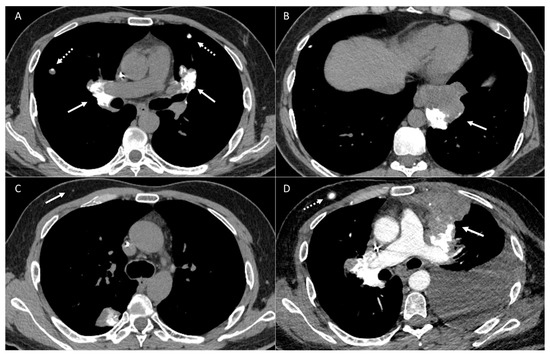

2.2. Vascular Metastasis

4. Mediastinum and Hilum

5. Cardiac and Major Thoracic Vessels

6. Chest Wall